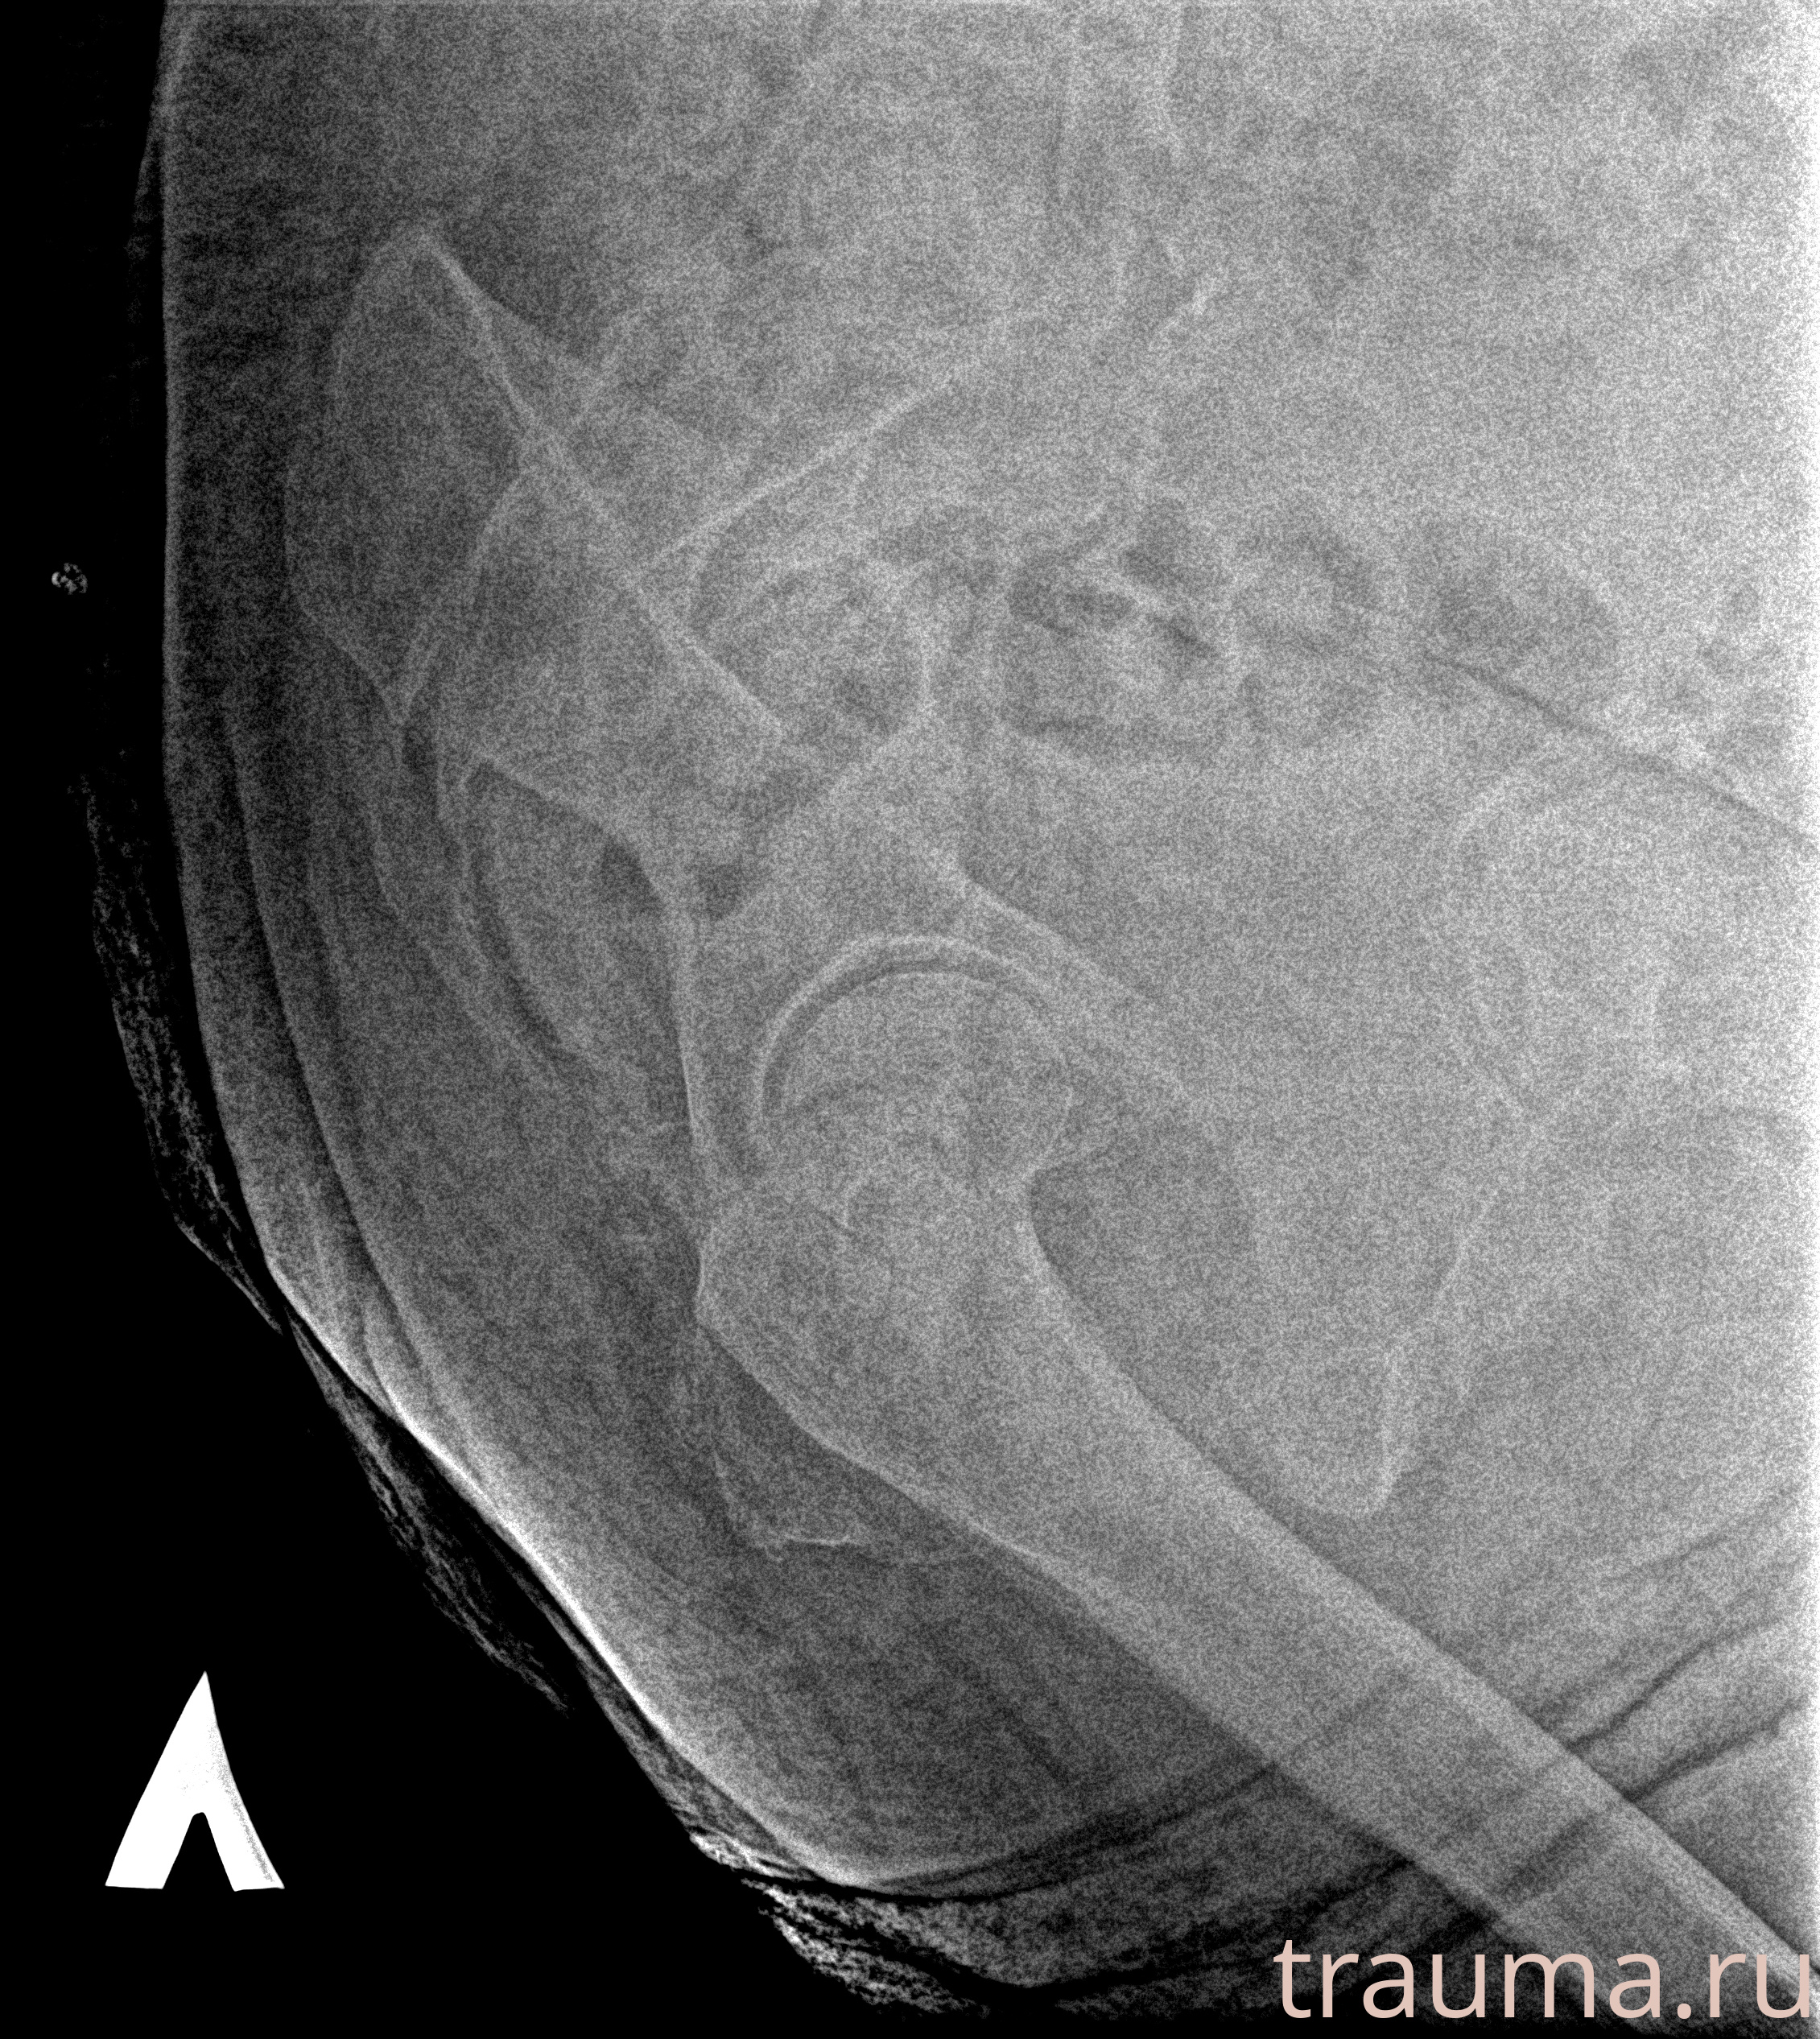

Рентген на дому: по вашему адресу приезжает врач-рентгенолог, травматолог-ортопед с мобильным рентгеновским аппаратом, проводит диагностику травмы или заболевания, делает необходимые рентгенограммы, дает рекомендации по дальнейшему лечению. Получить качественные снимки в домашних условиях возможно благодаря уникальной методике, разработанной МосРентген Центром для института  Склифосовского